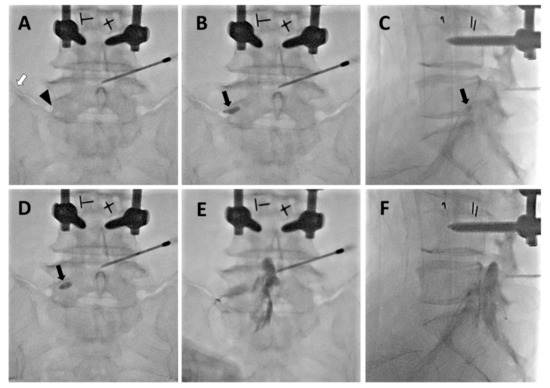

After confirming that the needle was positioned in the ipsilateral epidural space, a 2-Fr foraminal balloon catheter containing a removable guidewire was inserted in a caudal direction. The balloon catheter was steered to the lower aspect of the pedicle into the ventral epidural space and the neural foramen with foraminal stenosis (blue line in Figure 2B and arrowhead in Figure 3A). After checking the position of the catheter tip (fluoroscopic anteroposterior and lateral view), the guidewire was removed. After the air in the catheter had been removed, the catheter was connected to a 1 mL Luer-Lock syringe (Becton-Dickinson, Franklin lakes, NJ, USA) containing 0.13 mL of contrast medium (Omnipaque®, iohexol, GE Healthcare, Oslo, Norway). If air remained in the balloon catheter, the radiographic image could have some air artifact, which can be mistaken for a stenotic lesion. As shown in Figure 3B,C, the balloon procedure was performed from the outlet of the neural foramen to the central epidural space by gradually pulling the catheter backward. Each ballooning period did not exceed 5 s to avoid the possibility of ischemic nerve damage. The ballooning pressure was controlled according to the grade of the patient’s pain. If moderate to severe pain was noted during balloon inflation, no further attempt was made for safety reasons. In the main target site of foraminal stenosis, the balloon was inflated 2 or 3 times without moving the catheter. The catheter was moved only in the balloon-deflated state. After completion of the balloon adhesiolysis procedure, the foraminal balloon catheter was removed in a deflated state. The contrast medium was injected via the guide needle to confirm effective spreading of the contrast dye from the central epidural space to the left extraforaminal space (Figure 3D). A mixture of 1% lidocaine, 5 mg of dexamethasone, and 1500 IU of hyaluronidase (total volume of 3 mL) was injected into the target area. After injection, the guide needle was removed and a simple dressing was applied.

Figure 3. Serial fluoroscopic images of transforaminal balloon treatment via a retrograde interlaminar approach in patient H (see Table 1). (A) The foraminal balloon catheter with guidewire was inserted to the extraforaminal space through a guide needle, which was inserted via a retrograde interlaminar approach because of the patient’s high iliac crest (white arrow). The position of the foraminal balloon catheter can be checked with a fluoroscopic image of the guidewire (arrow head). (B) The foraminal balloon catheter was placed in the left L5–S1 intervertebral neural foramen. During ballooning with contrast medium, the grade of foraminal stenosis was visualized by the degree of balloon distortion (black arrow). (C) Lateral view in the state of Figure 3B. The inflated state of balloon in the intervertebral foramen is identified (black arrow). (D) Balloon treatment was performed by gradually pulling the catheter backward (black arrow). (E) After completion of the balloon procedure, the catheter was removed, and contrast medium was injected via the guide needle. The contrast medium is seen to spread well into the left L5–S1 intervertebral foramen and central epidural space. (F) Lateral view in the state of Figure 3E. The contrast medium is seen to spread well into the anterior and posterior epidural space.